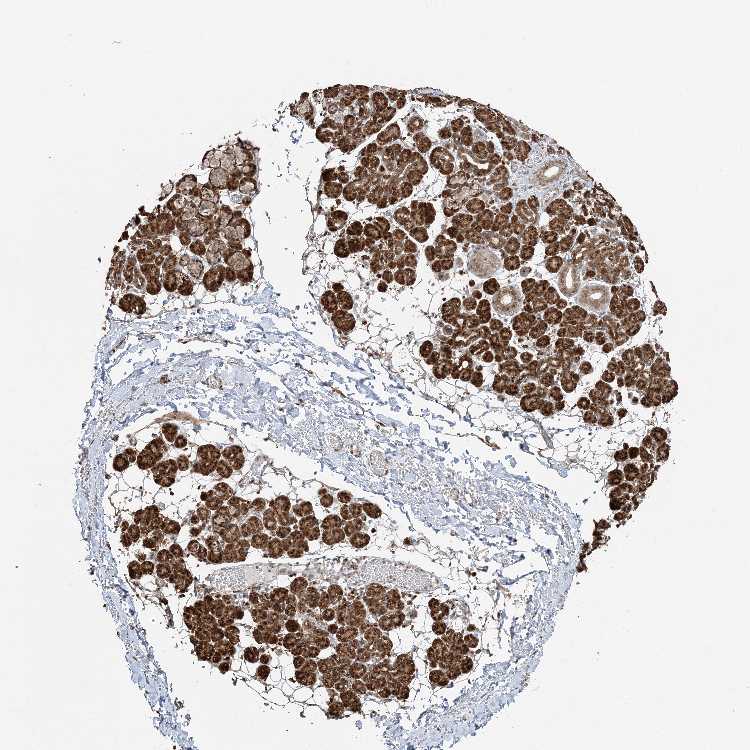

SALIVARY GLAND - Antibody stainingi

Antibody staining in the annotated cell types in the current human tissue is reported as not detected, low, medium, or high, based on conventional immunohistochemistry profiling in selected tissues. This score is based on the combination of the staining intensity and fraction of stained cells.

Each image is clickable and will lead to virtual microscopy that enables deeper exploration of all samples and also displays staining intensity scores, fraction scores and subcellular localization as well as patient and tissue information for each sample.

Antibody HPA047139Antibody HPA050539Antibody CAB034442Antibody CAB037251

Glandular cells HighHighHighHigh